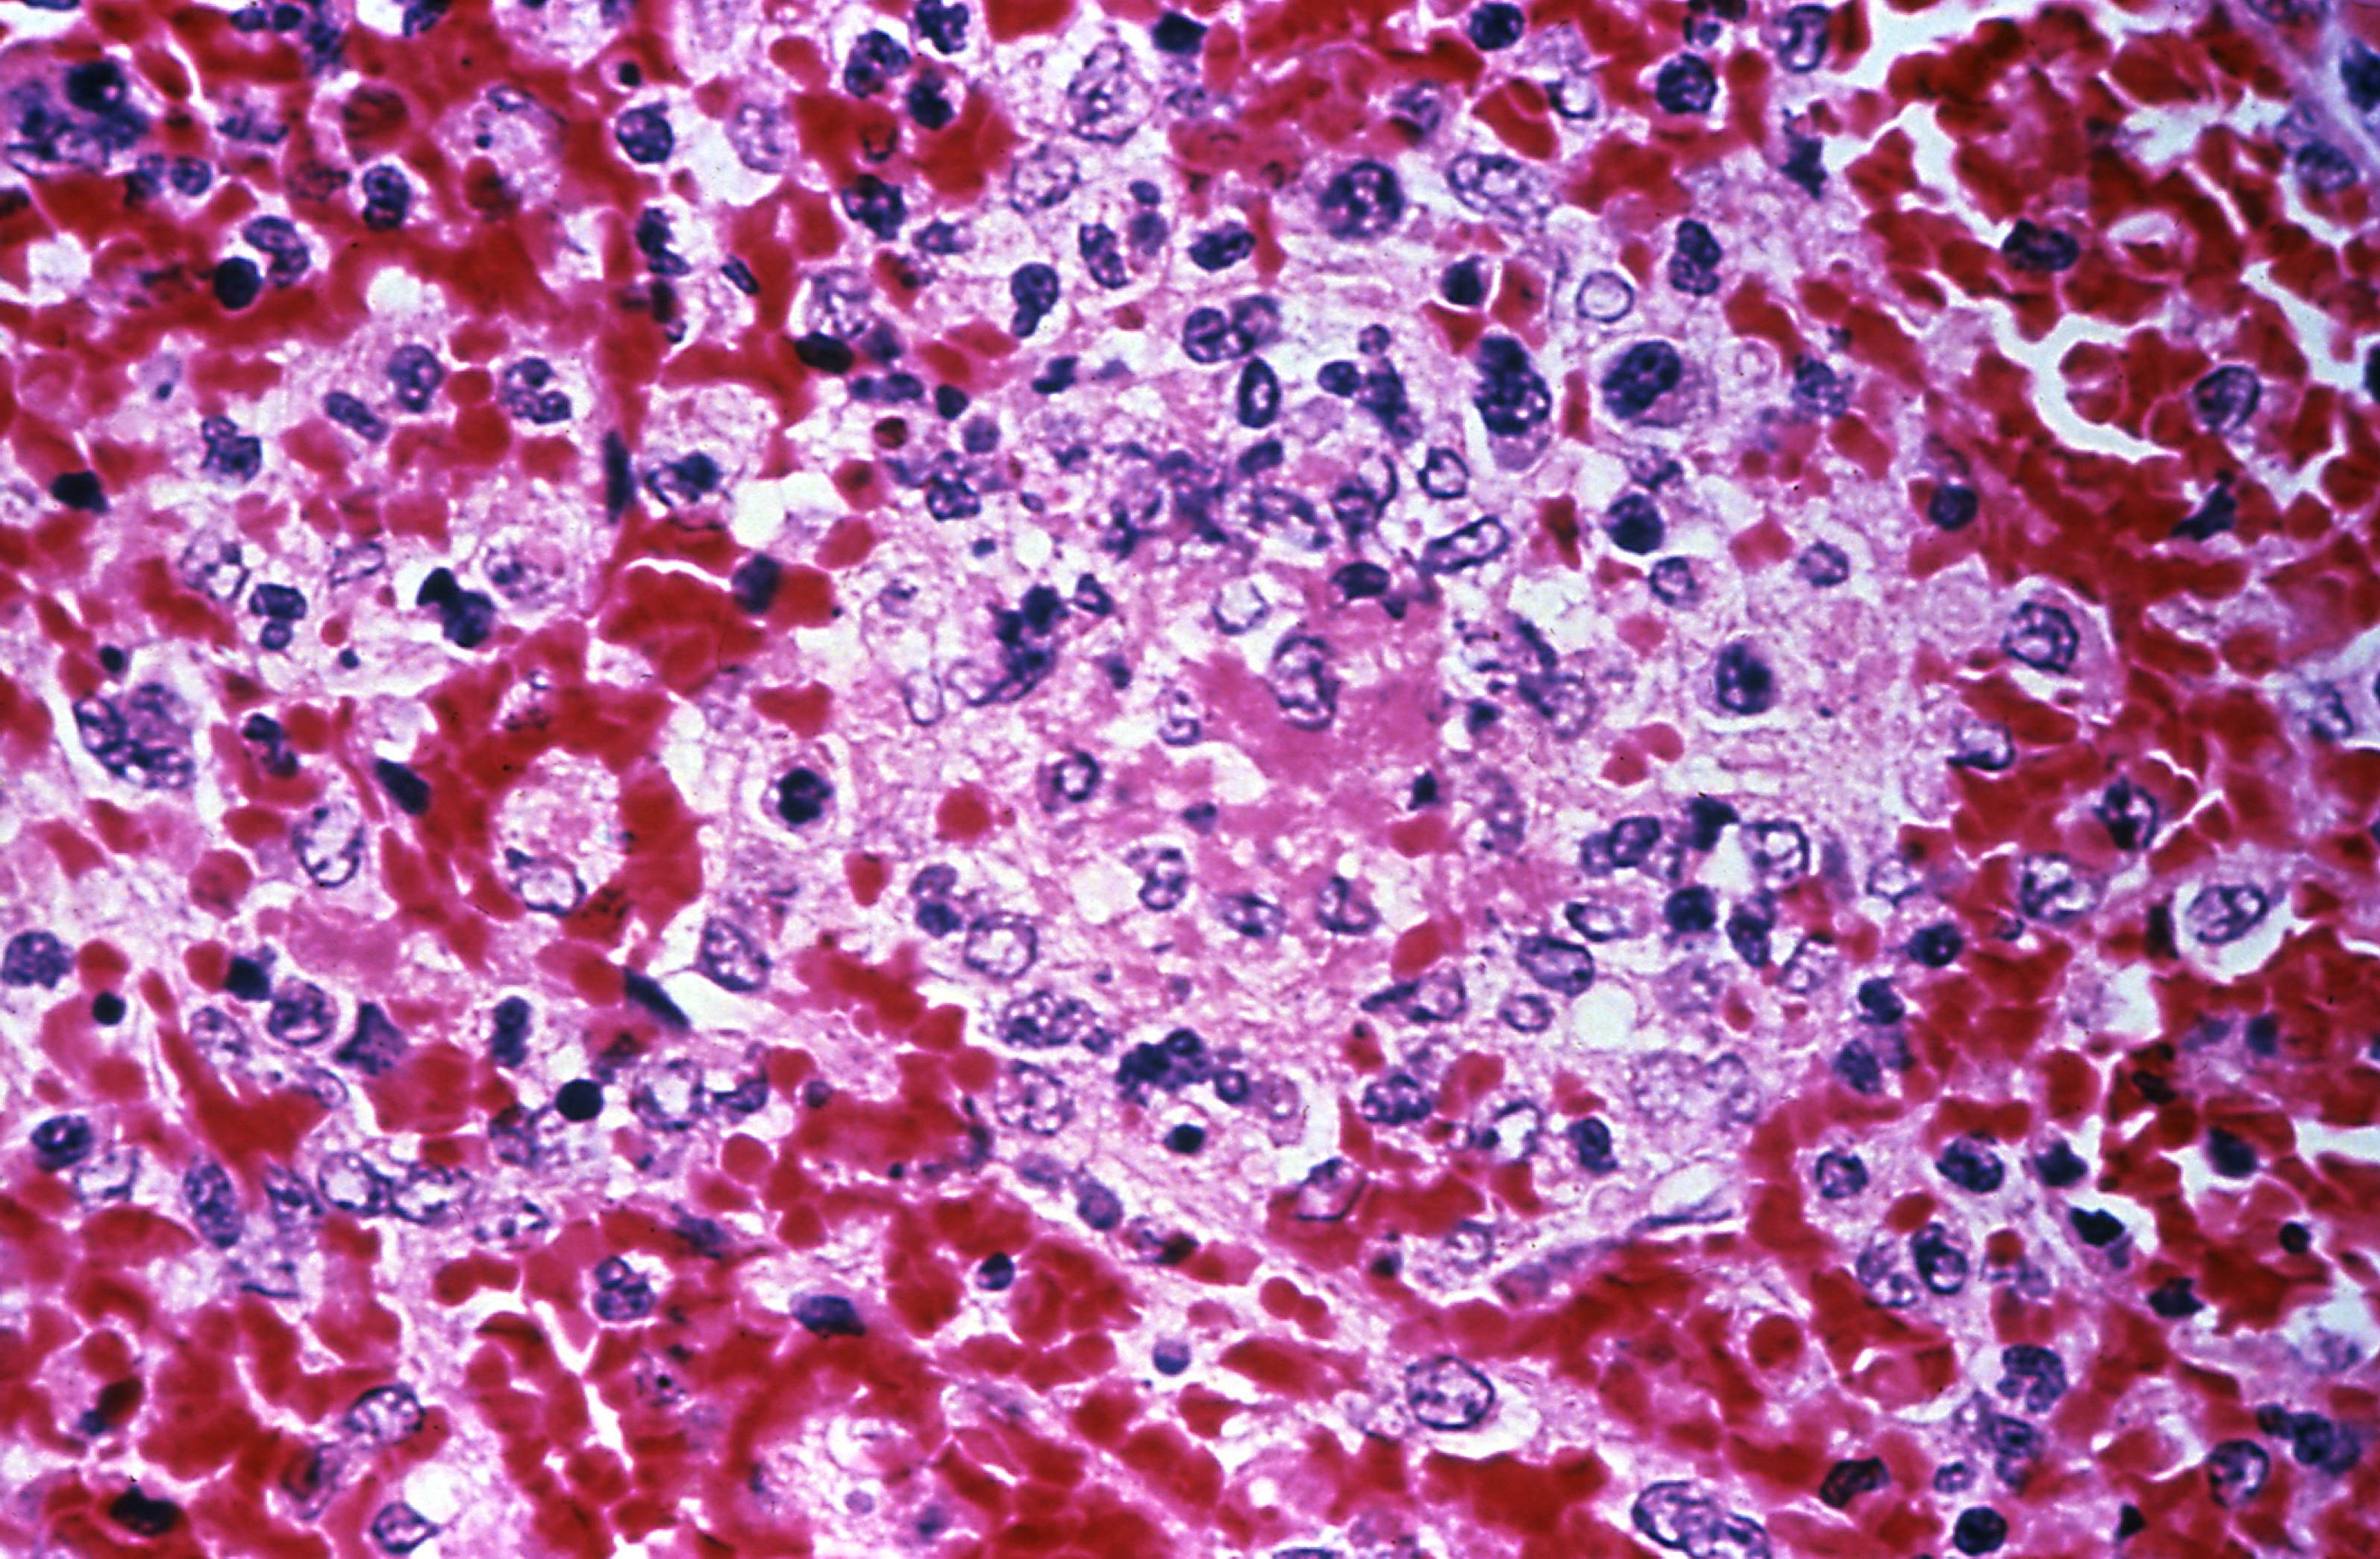

8. Fungal Meningitis

Fungal meningitis is usually caused by a rare fungus that spreads to the spinal cord via the blood. Anyone can be infected with fungal meningitis; however, it is most common in people with a weakened immune system or cancer. It is one of the most common causes of meningitis in Africa. Unlike viral and bacterial meningitis, fungal meningitis is not spread through contact with an infected person. It develops after a fungus reaches the bloodstream and spreads to another area of the body, such as the brain or spinal cord.